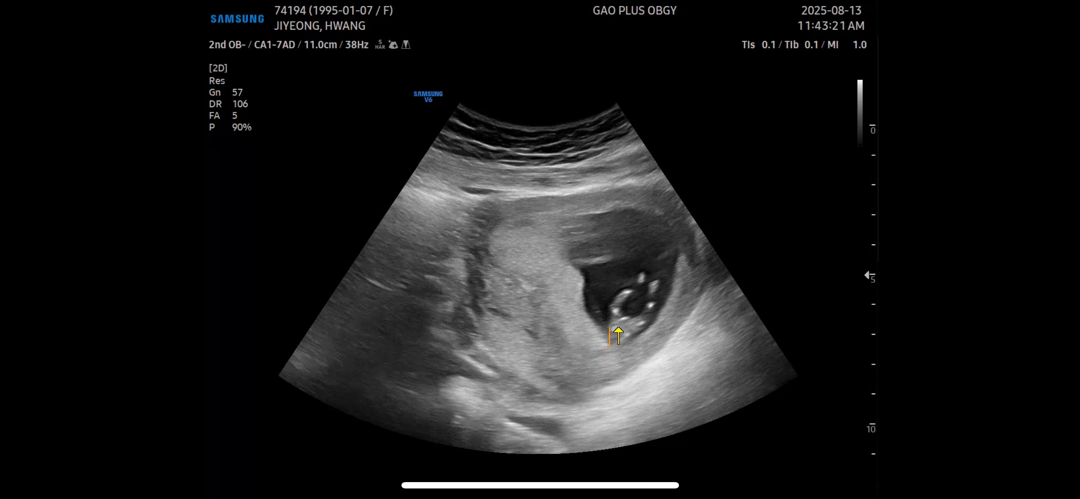

11주 4일 초음파 !

까꿍이 초음파 봤는데 다리사이에 아무것도 없어 ! 이때쯤 되면 애기 고추도 보인다던데 !! 혹시 딸인가 ?

16주차에 생기는 경우도 있어서 그때 가봐야 알아요~

16주에 반전있을수도있어요